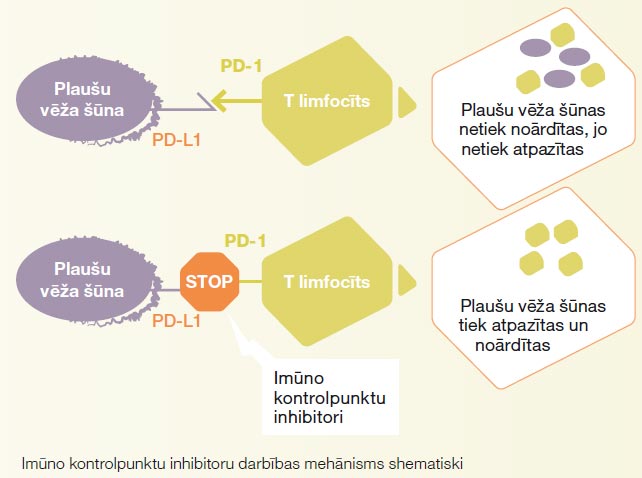

Imūnterapija

Imūnterapija ir inovatīva ārstēšanas metode. Imūnterapija palīdz organisma imunitātei atpazīt un noārdīt plaušu vēža šūnas, uzturot limfocītu aktivāciju caur speciālo receptoru bloķēšanu (skat. bildi).

Imūnterapija ir inovatīva ārstēšanas metode. Imūnterapija palīdz organisma imunitātei atpazīt un noārdīt plaušu vēža šūnas, uzturot limfocītu aktivāciju caur speciālo receptoru bloķēšanu..

Imūnterapiju pielieto plaši izplatīta vai metastātiska plaušu vēža ārstēšanai, kad nav iespējama efektīva lokāla terapija. Imūnterapija var tikt pielietota kā vienīgais medikaments, vai kombinācijā ar ķīmijterapiju. Lai novērtētu potenciālo imūnterapijas efektivitāti, veic PD-L1 receptoru noteikšanu plaušu vēža audu paraugā. Imūnterapijas medikamenti tiek ievadīti intravenozi ik 2–6 nedēļas.

Pretēji citotoksiskai ķīmijterapijai imūnterapija stimulē, nevis nomāc organisma imunitāti, tāpēc arī imūnterapijas blakusparādības ir saistītas nevis ar imunitātes novājināšanu, bet ar tās stimulāciju. Imunitātes stimulācija var notikt ne tikai pret vēža šūnām, bet arī pret organisma normālām šūnām. Tas izpaužas kā iekaisums, ko organisms izraisa pats pret sevi: ādas iekaisums (dermatīts), locītavu iekaisums (artrīts), vairogdziedzera iekaisums (tireoidīts), zarnu iekaisums (kolīts), plaušu iekaisums (pneimonīts) u.c. (skat. tabulu) Imūnterapijas blakusparādības, ja parādās, tad visbiežāk pirmo trīs mēnešu laikā no terapijas sākuma. Blakusparādības iedala smaguma pakāpēs, un visbiežāk novēro viegli- vidēji izteiktas blakusparādības. Tās ir labi ārstējamas ar kortikosteoīdiem – pretiekaisuma medikamentiem tablešu vai injekciju veidā.

Imūnterapiju pielieto plaši izplatīta vai metastātiska plaušu vēža ārstēšanai, kad nav iespējama efektīva lokāla terapija. Imūnterapija var tikt pielietota kā vienīgais medikaments, vai kombinācijā ar ķīmijterapiju. Lai novērtētu potenciālo imūnterapijas efektivitāti, veic PD-L1 receptoru noteikšanu plaušu vēža audu paraugā. Imūnterapijas medikamenti tiek ievadīti intravenozi ik 2–6 nedēļas.

Pretēji citotoksiskai ķīmijterapijai imūnterapija stimulē, nevis nomāc organisma imunitāti, tāpēc arī imūnterapijas blakusparādības ir saistītas nevis ar imunitātes novājināšanu, bet ar tās stimulāciju. Imunitātes stimulācija var notikt ne tikai pret vēža šūnām, bet arī pret organisma normālām šūnām. Tas izpaužas kā iekaisums, ko organisms izraisa pats pret sevi: ādas iekaisums (dermatīts), locītavu iekaisums (artrīts), vairogdziedzera iekaisums (tireoidīts), zarnu iekaisums (kolīts), plaušu iekaisums (pneimonīts) u.c. (skat. tabulu) Imūnterapijas blakusparādības, ja parādās, tad visbiežāk pirmo trīs mēnešu laikā no terapijas sākuma. Blakusparādības iedala smaguma pakāpēs, un visbiežāk novēro viegli- vidēji izteiktas blakusparādības. Tās ir labi ārstējamas ar kortikosteoīdiem – pretiekaisuma medikamentiem tablešu vai injekciju veidā.